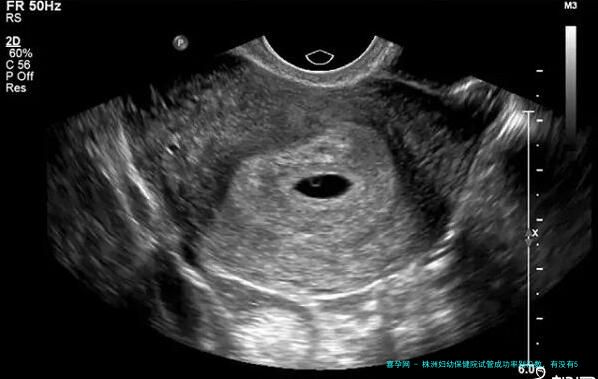

株洲市妇幼保健院生殖医学中心成立于2006年,2019年此医院获得展开试管婴儿技术的试运行资质,时隔一年就获取了正规运转资质。如此看来,此医院生殖医学科实力或是相较强的,这里就为大家阐述一下株洲妇幼不孕不育科:

1. 技术:开展了夫精宫腔内人工授精、第一代试管婴儿和第二代试管婴儿技术;2. 医疗团队:拥有一支治疗男、女性不孕不育,生殖内分泌疾病及开展辅助生殖技术的团队,其中比较知名的有周春慧、龙文香、易艳萍等等生殖专家;3. 成功率:经过这几年的不懈努力,该医院试管成功率可以达到50%左右,该医院夫精人工授精助孕成功率也在国内先进水平,稳定在15%左右。Tips: